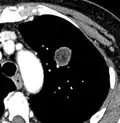

- Enhancement: If the exam is done as a combined non-contrast and contrast CT, a solitary nodule with an enhancement off less than 15 Hounsfield units (HU), whereas a higher enhancement indicates a malignant tumor (with a sensitivity estimated at 98%).[12]

- Areas of fatty tissue (−40 to −120 HU) indicates a hamartoma. However, only about 50% of hamartomas are fat containing.[9]